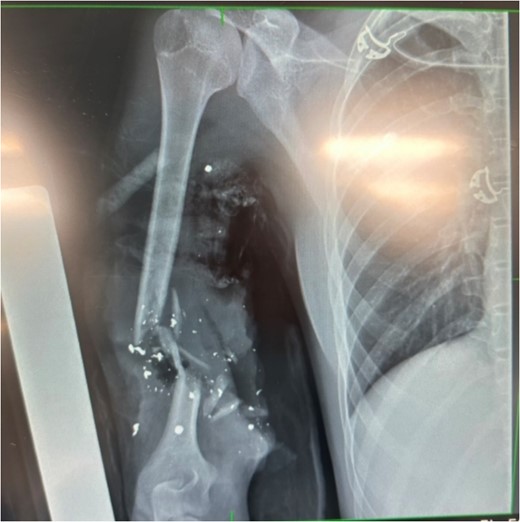

Identification of anatomical structures and damage sustained (Fig. 1)

10 cm brachial artery defect, no active bleeding.

Radial and ulnar nerves identified and preserved.

Medial nerve likely transected.

3-4 cm humeral defect.

Identification of important structures and damage sustained; torniquet in situ; green arrow: medial brachial cutaneous nerve; blue arrow: ulnar nerve.

X-ray showing extent of damage to humerus; bullet shrapnel visible.